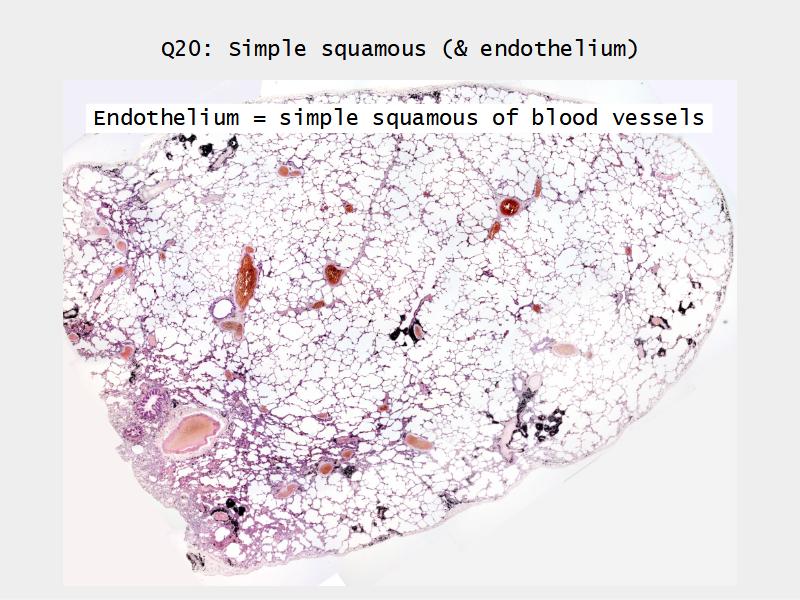

Slides: Respiratory System

- Slide 72 & 74: Lung

- Alveoli

Lungs